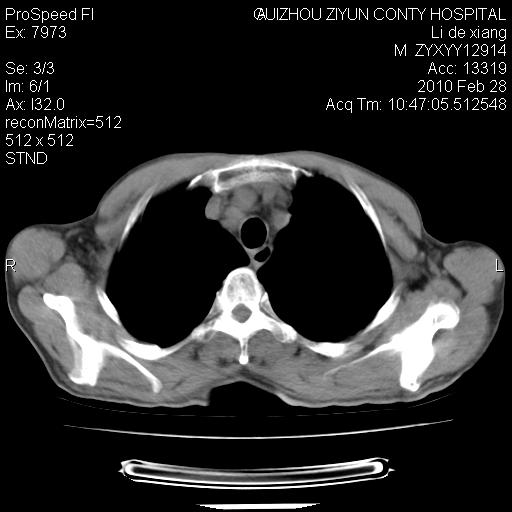

标题: CT24776:男 71Y 咳嗽咳痰胸痛两月,伴声音嘶哑。 [打印本页]

标题: CT24776:男 71Y 咳嗽咳痰胸痛两月,伴声音嘶哑。

纵膈淋巴结肿大 不除外占位性阻塞

左肺门部肿块,伴左上肺斑块影,周边模糊,支持左肺中央型肺癌伴节段性不张及阻塞性肺炎,结合支气管镜检查。

左上叶支气管狭窄,阻塞性病变,肺门肿块,纵隔及肺门淋巴结增大,中央性肺癌

左肺中央型肺癌并阻塞性改变、纵膈 淋巴结转移